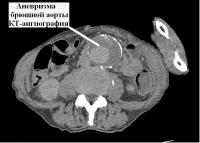

В Коломенскую больницу поступил 79-летний мужчина с выраженным болевым синдромом в животе. После проведения ультразвукового исследования, а затем компьютерной томографии с контрастным усилением врачи диагностировали аневризму брюшного отдела аорты. Патология представляет собой локальное расширение сосуда с постепенным истончением его стенки. У пациента ее диаметр превышал 10 см при нормальном диаметре аорты 18–22 мм.

Аневризма брюшной аорты – патология не редкая, но опасная тем, что долгое время никак себя не проявляет. Может дать о себе знать только на этапе осложнений – в период, когда близка к разрыву. Без своевременной медицинской помощи это может привести к летальному исходу.